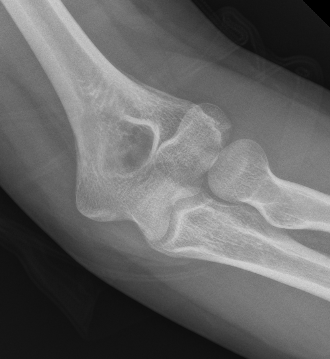

Capitellum fracture with radial head fracture

Capitellum fracture with radial head dislocation due to LCL injury

Concomitant injuries

Radial head

- 79 capitellar fractures

- 24% had a radial head fracture as well

LCL

- 27 capitellum fractures treated with surgery

- 41% had associated LCL injuries

- 7/11 LCL injuries were avulsion fractures of the lateral epicondyle